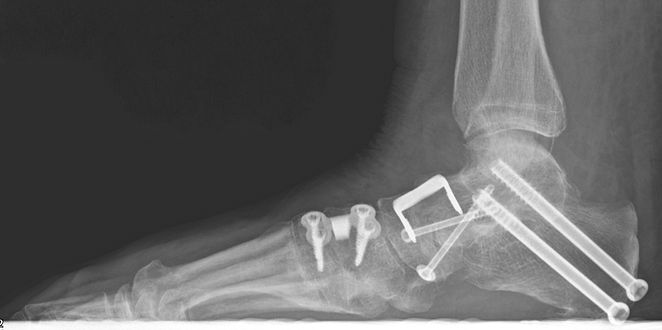

Osteotomy - the heel bone (calcaneus) is cut and shifted to reduce the deformity. In patients with more severe deformities an additional osteotomy of a bone in the mid foot (cuneiform) is also made. The bones are held by internal plates, screws or staples (see X-rays A and B).

Fusion - done in cases with rigid deformities or presence of arthritis. Fusion involves removing cartilage in the joint and fixing the bones to each other in a corrected position. The bones are held by internal plates or screws (see X-ray C).

Xrays B (Before and after) showing plate and staples following Evans osteotomy & Fusion of 1st TMTJ to realign flat foot

Xrays C showing subtalar and talonavicular joint fusions and Cotton osteotomy to realign flat foot